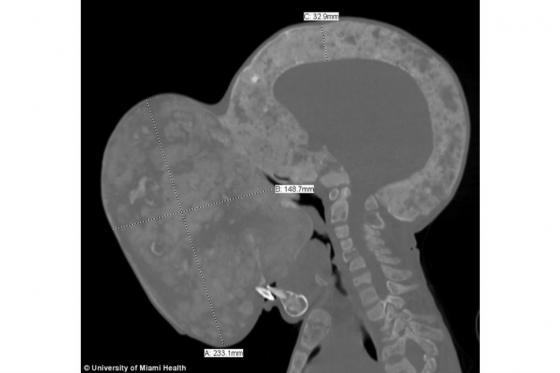

El menor cubano Emanuel Zayas, quien fue operado de un tumor en su cara del tamaño de una pelota de baloncesto, falleció, según confirmó uno de los médicos que intervino en su operación.

Emanuel, de 14 años, fue diagnosticado desde pequeño con un síndrome poco común que afecta los huesos, la piel y el sistema hormonal, lo que le generó un tumor de 4,5 kilogramos en el rostro. El tumor lo ponía en riesgo de asfixia o de sufrir una fractura en el cuello.